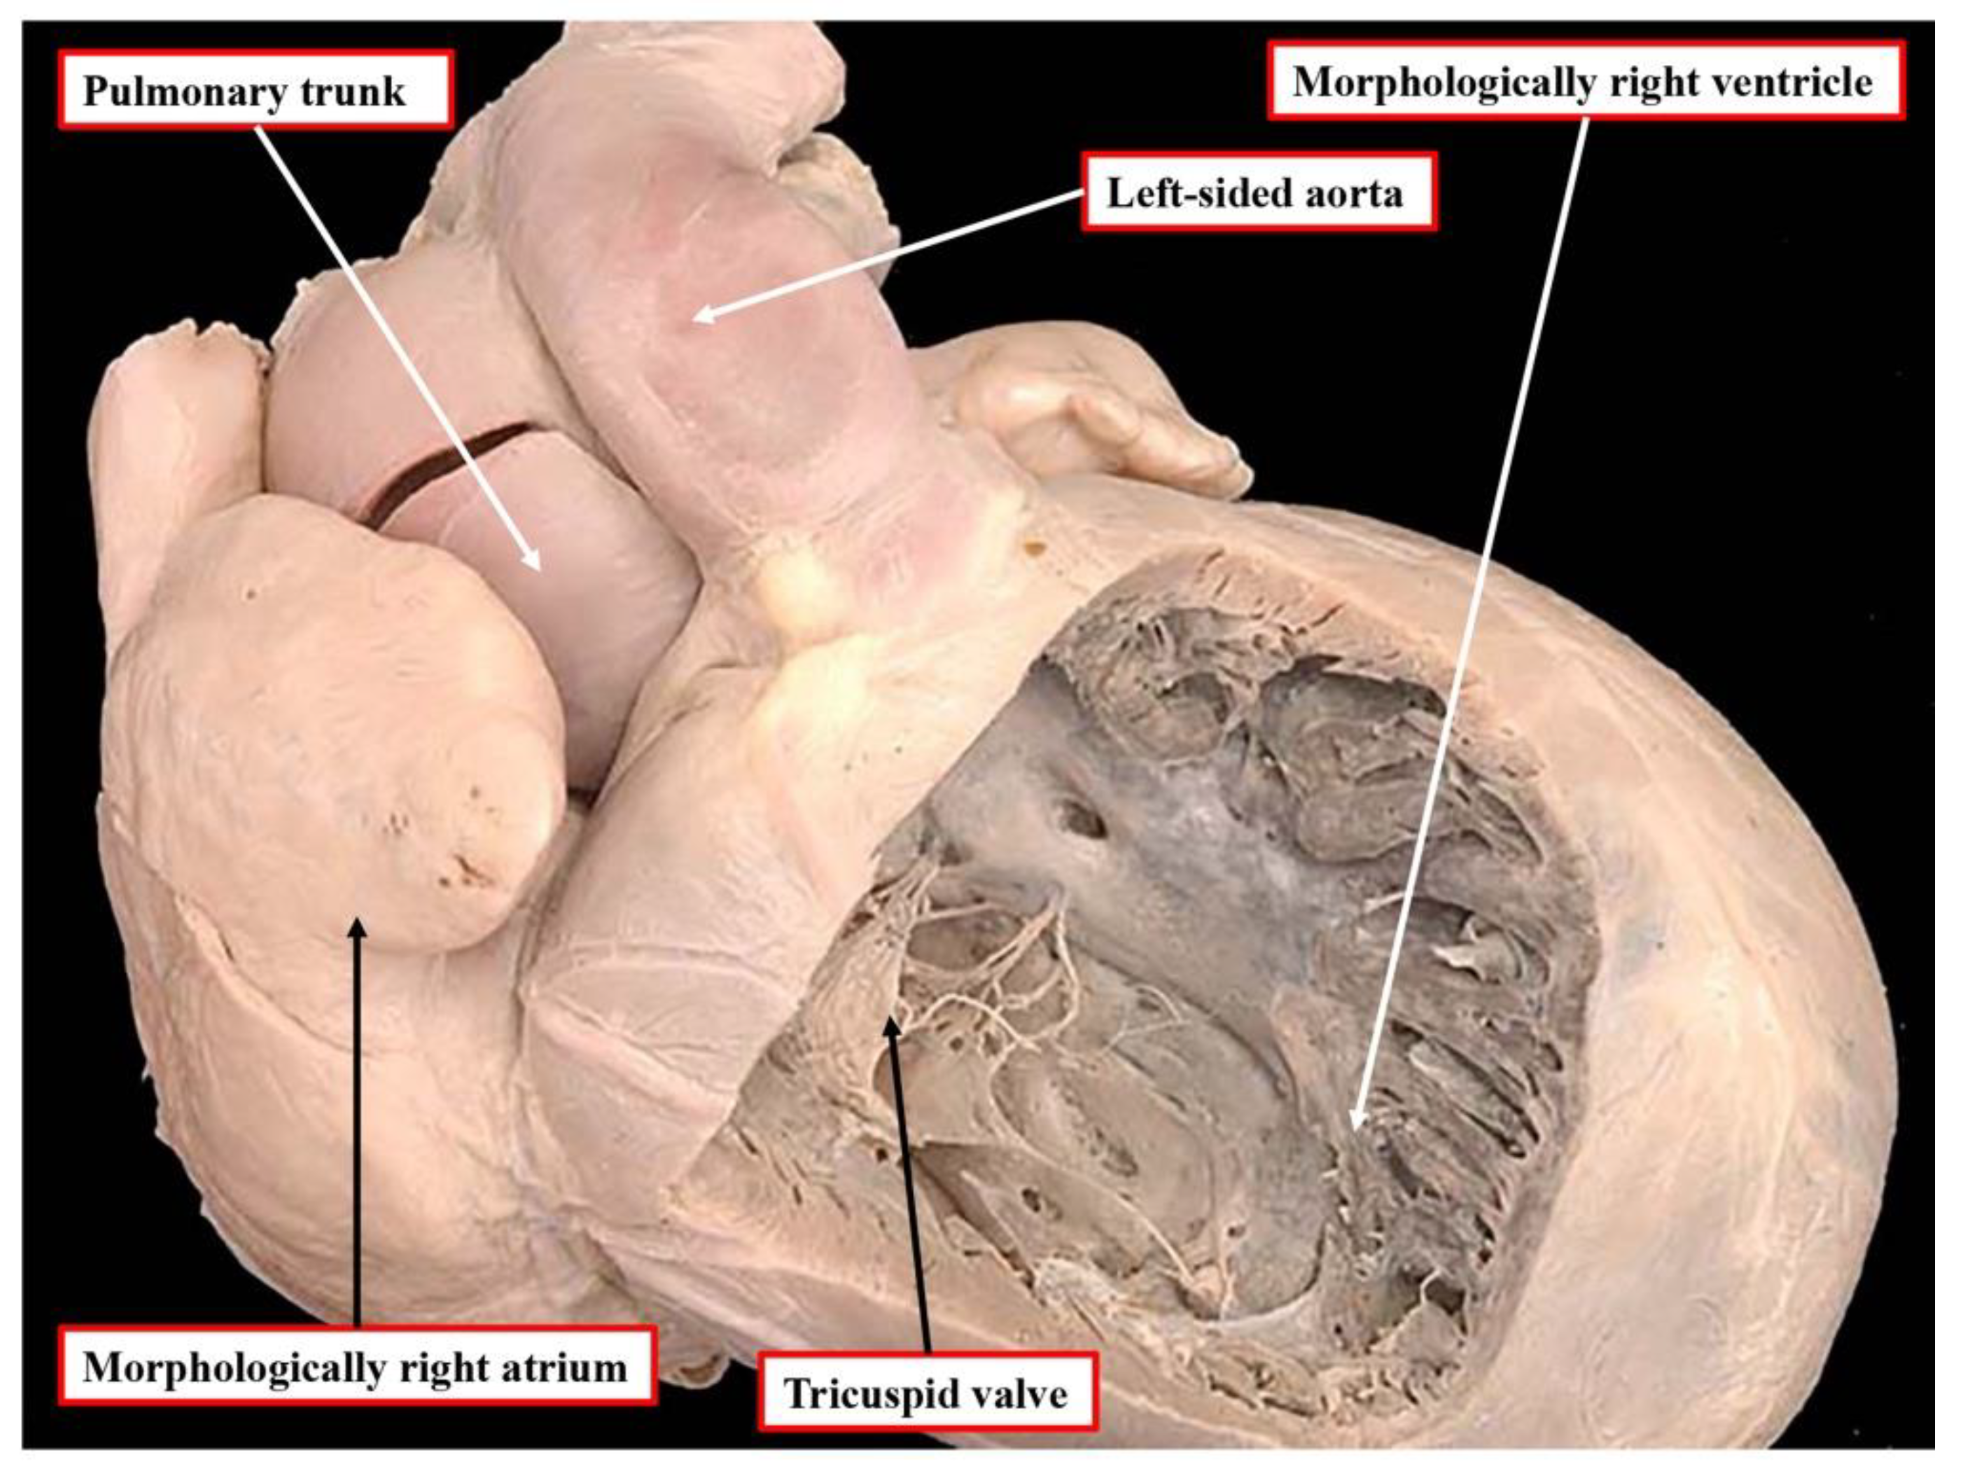

7. What about Incongruent Segmental Arrangements at Ventriculo-Arterial Level?

When the segmental approach was first introduced, it was not always easy to establish the fashion in which the cavities of the segments were joined together across the atrioventricular and ventriculo-arterial junctions during clinical investigation. In these early days, prior to the introduction of cross-sectional echocardiography, it was conventional to use the “loop rule” to determine the variants of transposition. Thus, in individuals with usual arrangement, the finding of a left-sided aorta arising from the morphologically right ventricle came to be considered an indicator of the presence of congenitally corrected transposition. Indeed, in some centres, even nowadays, “l-transposition” is used as if synonymous with congenitally corrected transposition. The danger of using this approach had already been identified prior to the widespread use of echocardiography. In a seminal study conducted at Great Ormond Street, in collaboration with Dr Van Praagh himself, it was shown that in individuals with regular transposition, in other words, concordant atrioventricular and discordant ventriculo-arterial connections, around one-sixth of those having usual atrial arrangement have left-sided aortas (

Figure 7). This investigation, unfortunately, was never published as a full manuscript and is available only in abstract form [

16]. For those using the Van Praaghian segmental sets, the segmental disharmony does not create the problems encountered for the atrioventricular junctions. This is because the arrangement, as shown in

Figure 7, would be described as transposition {S,D,L}. The inference to be made from the combination of {S,D,*) is that the atrioventricular connections are concordant. The description of transposition indicates that the ventriculo-arterial connections are discordant. Similar ventriculo-arterial disharmony can be found in the setting of the double outlet right ventricle. Thus, in most instances of double outlet right ventricle with usual atrial arrangement and concordant atrioventricular connections, the aortic root is either normally related to the pulmonary trunk or else anterior and rightward. In the past, the anterior location of the aorta would be considered by some as indicative of the presence of “transposition”.

Those using both the segmental and sequential segmental approaches now accept that transposition is synonymous with discordant ventriculo-arterial connections. The finding of an anterior and left-sided aorta can also rarely be found when both arterial trunks arise from the right ventricle when there is usual atrial arrangement and concordant atrioventricular connections. This is another example of disharmony at the ventriculo-arterial junctions. It would properly be described by those using the segmental approach as a double outlet right ventricle {S,D,L}. It follows that it is inappropriate to consider an anterior and left-sided aorta as being indicative of congenitally corrected transposition. Most individuals with congenitally corrected transposition do have left-sided aortas, but not all. Anterior and right-sided aortas are the rule when congenitally corrected transposition is found in individuals with a mirror-imaged atrial arrangement. It also follows, therefore, that “d-transposition” should not be used as a synonym for individuals having concordant atrioventricular and discordant ventriculo-arterial connections.